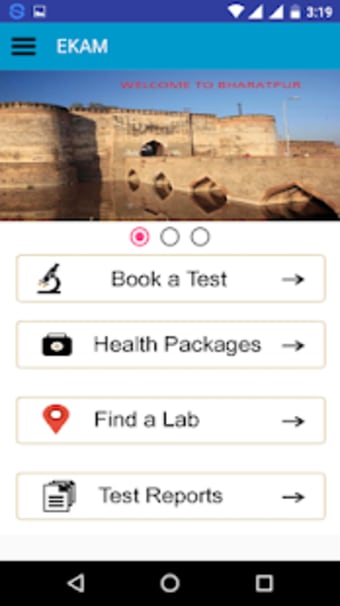

Бесплатная программа для Android от Gayatri Softwares.

Ekam– это бесплатное приложение для Android, относящееся к категории "Медицина".

Это программное обеспечение было опубликовано на Softonic 16 января 2020 года, и у нас еще не было возможности его протестировать.

Ekam требует Android 9.0 или выше. Текущая версия программного обеспечения — 1.0, и вы можете получить ее только на английском языке.